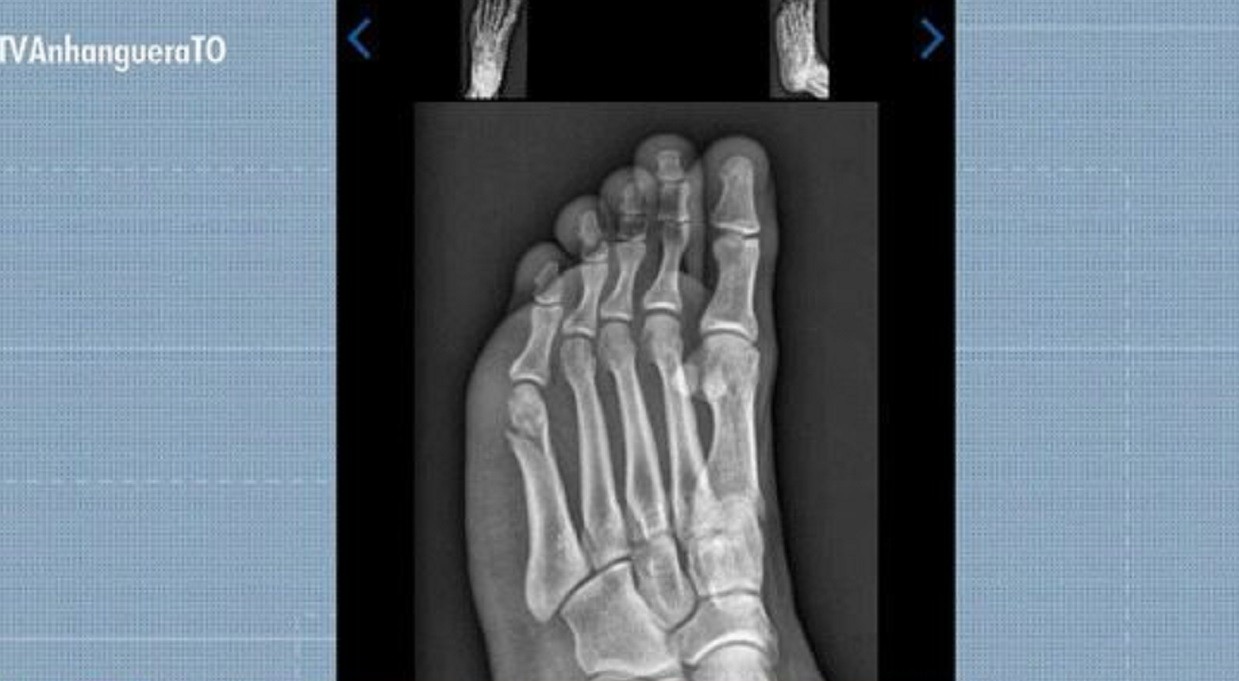

“Pensei que não ia conseguir. Consegui fazer as outras etapas, mas no dia da corrida eu estava bastante nervoso. Quando estava faltando mais ou menos 20 ou 30 segundos olhei no meu relógio e estava faltando completar uma volta de 200 metros, falei ‘ah, não vai dar’. Porque por mais que o tempo passe rápido lá na hora, tudo na sua mente passa devagar”, contou Gabriel em entrevista à TV Anhanguera.

Mesmo em dúvida se conseguiria completar a prova, Gabriel continuou, afinal já havia passado pelas outras etapas do TAF. Ele concluiu a prova faltando três segundos para o limite.

Concurseiro concluiu prova de corrida do TAF com fratura no pé

Reprodução/TV Anhanguera